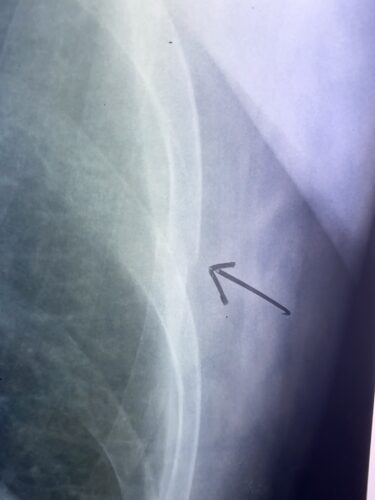

骨折・脱臼

肋骨骨折、つらい痛みを乗り越える。牛久市・周辺地域のあなたのための保存療…